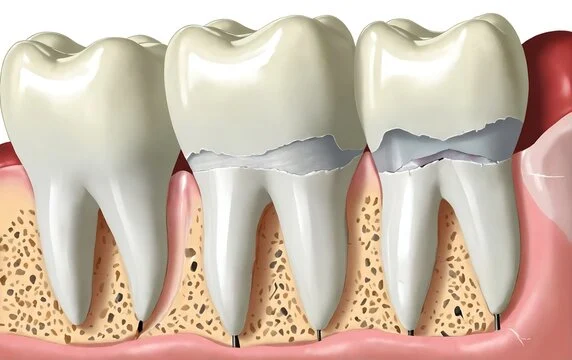

Gentle and Effective Tooth Extractions for a Healthy Smile

Tooth extraction is a common dental procedure necessary for removing teeth that are severely decayed, damaged, or causing alignment issues. At Vitalis Dental, our experienced oral surgeons perform tooth extractions with precision and care, ensuring minimal discomfort and optimal healing.

Strengthen Your Jawbone for Long-Lasting Dental Implants

Bone grafting is a critical procedure for patients who lack sufficient bone density or volume in their jawbone to support dental implants. At Vitalis Dental, we utilize advanced bone grafting techniques to rebuild and enhance your jawbone structure, ensuring a stable foundation for successful implant placement.

At Vitalis Dental, we use high-quality bone graft materials, including autografts (your own bone), allografts (donor bone), and synthetic bone substitutes. Our oral surgeons will determine the best material for your specific needs to ensure optimal results.